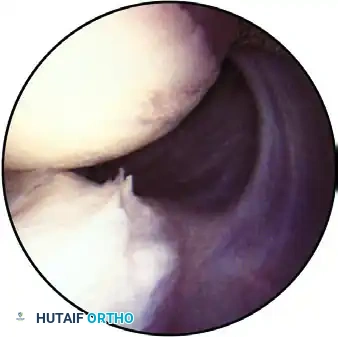

With the patient in the lateral decubitus position and the camera upright, the glenoid is oriented horizontally. The systematic examination begins superiorly.

Observation of the superior part of the shoulder joint, demonstrating the biceps tendon inserting into the superior labrum. The humeral head is positioned superior-right, and the glenoid is inferior.

The arthroscope is advanced to evaluate the articular cartilage of the glenoid and the humeral head. The humeral head is dynamically assessed by internally and externally rotating the arm, observing for chondromalacia, osteochondral defects, or traumatic lesions.

On the central glenoid articular surface, a distinct area of thin or absent articular cartilage may be observed. This "bare spot" is a normal anatomical finding and must not be misidentified as an osteochondral defect.